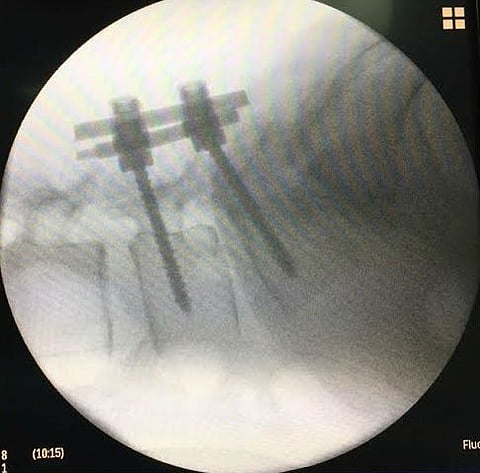

نجح فريق قسم جراحة المخ والأعصاب بمستشفى حفر الباطن المركزي، في إجراء عملية جراحية لتثبيت الفقرات القطنية لمريضة في العقد الخامس من عمرها، تعاني من انزلاق بسبب زيادة الوزن؛ مما سبّب لها صعوبة في الحركة.

وكانت المريضة قد أُدخلت المستشفى، وتم عمل الفحوصات والإجراءات الطبية الأولية، وتم التدخل الجراحي لتثبيت الفقرات؛ برغم ما صاحَبَ العملية من صعوبات أثناء العملية؛ نظراً للوزن الزائد الذي يمنع سهولة الوصول إلى العمود الفقري وتثبيت الفقرات.

وقد تكللت العملية بالنجاح التام ولله الحمد، وتماثلت المريضة للشفاء وخرجت بعد خمسة أيام من إجرائها بدون أي مضاعفات جانبية، بفضل الله.